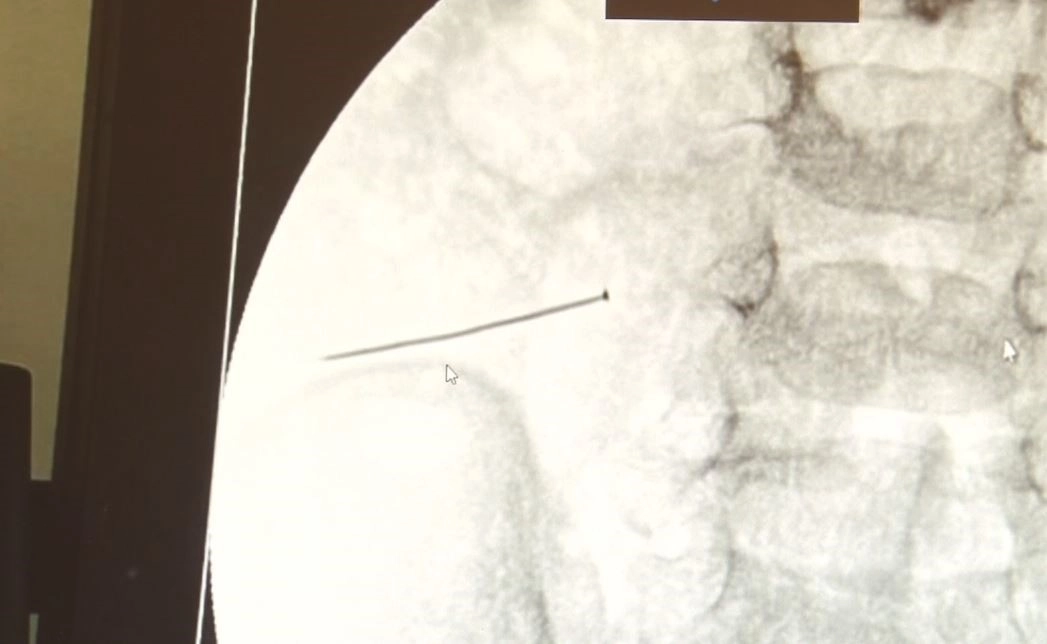

İstanbul’da 2 yaşındaki çocuk iddiaya göre toplu iğne yuttu sonrasında adeta karın ağrısıyla yerinde duramaz hale geldi. Babaanne, küçük çocuğun şikayetleri üzerine Şehit Prof. Dr. İlhan Varank Sancaktepe Eğitim ve Araştırma Hastanesi’ne götürdü. Burada yapılan tetkiklerde 2 yaşındaki çocuğun ince bağırsağında yaklaşık 3 santimlik toplu iğne olduğu ve bağırsağı deldiği belirlendi. Görüntülemeler sonrası 30 Ekim akşamı Çocuk Cerrahisi Kliniği Eğitim ve İdari Sorumlusu Doç. Dr. Sefa Sağ ve ekibi hemen ameliyata girdi. Başarılı operasyonla iğne olduğu noktadan alınırken aile de rahat bir nefes aldı. Doç. Dr. Sağ ise taburcu edilen hastasının durumuna ilişkin bilgi verirken yabancı cisim yutmalarına karşı ailelere önemli uyarılarda bulundu. "Yaklaşık 3 santim toplu iğnenin ince bağırsağı deldiğini gördük" Çocuklarda yabancı cisim yutulmasına yönelik konuşan ve hastasına ilişkin bilgi veren Doç. Dr. Sefa Sağ, "Soluk borusuna kaçması durumunda çocuğun Allah göstermesin ölümüyle veya ömür boyunca yatağa bağımlı kalmasıyla neticelenebilecek sonuçlar doğurabiliyor. Yutulması durumunda da gastrointestinal sistemin herhangi bir yerine takılmadığı müddetçe ekseriyâ yabancı cisimlerin dışarıya çıkmasını bekliyoruz. Yabancı cisim yutulmasını 2 grupta inceleyebiliriz. Sıvı ve katı cisimler olarak sıvı; evde kullanılan kimyasal temizlik malzemelerinin yutulması çok ciddi problemler oluşturabilmekte. Ağızda, yemek borusunda ve midede yanıklar meydana getirebilmekte. Uzun dönemde çocukların hayat kalitesini oldukça etkileyen sonuçlar doğurabilmekte. Katı cisimlerden de ekseriyâ kendiliğinden çıkmasını bekleriz ancak böyle delici, kesici aletlerin yutulmasında ise herhangi bir bağırsağın veya gastrointestinal sistemin bir parçasında delinmeler meydana getirebiliyor. Bu çocuğumuzda da aynen böyle bir hadise meydana gelmişti. Sanırım 1 gün önce ailenin yuttuğunu tahmin ettiği bir yabancı cisim; toplu iğne. Ertesi gün bağırsakta delinmeyle sonuçlanmış ve çocukta da ciddi semptomlar meydana getirmişti. Bu şekilde hasta bize başvurdu. Tetkikler sonucunda yabancı cismi tespit ettik, semptomları ve bulgularına göre de çocuğu ameliyata aldık. Yaklaşık 3 santim boyunda bir toplu iğnenin ince bağırsağı deldiğini, ince bağırsaktaki içeriğin de karın içerisine dolduğunu gördük. Ameliyatı başarılı bir şekilde tamamladık, yaklaşık 1 saat süren bir ameliyattı" dedi. "Çocuğun ölümüyle sonuçlanabilecek bir hadiseydi" Heimlich Manevrasının herkes tarafından bilinmesi gerektiğini aktaran Doç. Dr. Sağ, sözlerine şöyle devam etti, "Soluk borusu haricinde bir yutulma şüphesi varsa mutlaka sağlık profesyonellerinin haberi olması gerekiyor. Sıklıkla gördüğümüz mıknatıs yutma, özellikle çoklu yutmalarda bağırsaklarda delinmeleri sıklıkla görebiliyoruz. Saat pilleri, disk piller mide sıvısıyla etkileşime girip midede delinmeler meydana getirebiliyor. İçerdiği cıva gibi çeşitli kimyasalların vücuda karışmasıyla çocuk sağlığını çok ciddi tehlikeye sokabilecek sonuçlar doğurabiliyor. Dünya Sağlık Örgütü’ne göre 1 milyondan fazla çocuk 1 yıl içerisinde ev kazalarından kaybediliyor. Bunları minimuma indirmek mümkün. Evdeki temizlik maddelerinin kilitli dolaplarda saklanması veya çocuğun yutabileceği maddelerin ise çocuktan uzak tutulması önemli çünkü çocuklar belli bir yaş grubuna göre ağzıyla bazı cisimleri tanımayı tercih edebiliyor. Bu cisimler de soluk borusuna veya yemek borusundan gastrointestinal sisteme kaçabiliyor, dikkatli olmak çok önemli. Hastamız, 2 yaşındaydı, fark edilmemesi çok mümkün değil çünkü çocukta çok ciddi bir karın ağrısı, kusma vs. söz konusuydu, ameliyatını yapmasaydık Allah göstermesin çocuğun ölümüyle sonuçlanabilecek bir hadiseydi" Öte yandan, yaklaşık 3 santimlik toplu iğne filme yansıyan görüntüsüyle gözler önüne serildi.